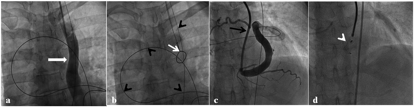

Figure 3. Selected images demonstrating device deployment. (A) Left internal jugular venous injection shows left superior vena cava (thick white arrow). (B) Exchange guidewire (black arrowheads) was exteriorized by using a goose-neck snare (white arrow), thus forming the arteriovenous loop (black arrowheads). (C) A Cook sheath was introduced over the guidewire and injection via sheath opacified the coronary sinus end of fistulous tract. (D) The device was deployed at the narrow neck just before it drains into the coronary sinus (click thumbnail to view larger image).

In view of the symptoms, percutaneous closure of the fistula was planned. Because of close proximity of the CAF to the left internal jugular vein (IJV) and perceived ease of fistula closure, we used the left IJV access and the LSVC approach through the coronary sinus for the device closure. From the right femoral artery approach, a 6 Fr left coronary catheter (Judkins; Cordis Corporation) was used to engage the left coronary sinus. Selective coronary angiogram was done to delineate the fistulous tract. A 0.035˝ x 360 cm exchange guidewire (Terumo Corporation) was introduced into the circumflex coronary artery and advanced into the fistula beyond its narrowest point (Figure 3A). The guidewire was negotiated into the coronary sinus and then into persistent LSVC (Figure 3A). From the left IJV, a 7 Fr sheath was introduced. Using a goose-neck snare (Amplatz goose neck), the Terumo guidewire in the LSVC was exteriorized out of the left IJV (Figure 3B) and an arteriovenous wire loop was established. Subsequently, a 7 Fr sheath (Cook, Inc) was introduced over the exchange wire from the left IJV through the LSVC, coronary sinus and positioned in the fistula (Figure 3C). A 10 x 8 mm patent ductus arteriosus (PDA) Lifetech device (Seercare; Lifetech Scientific Co, Ltd) was deployed at the narrowest point in the distal part of the fistula, 1-2 cm from the drainage point into the coronary sinus (Figure 3D).